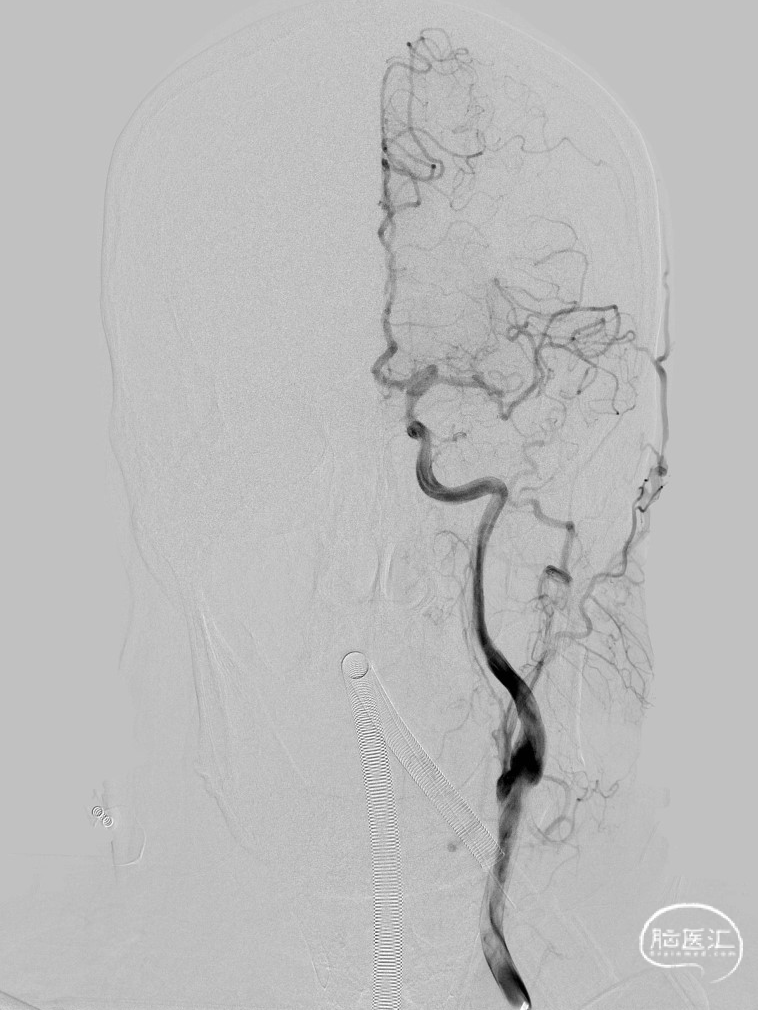

DSA检查提示左侧大脑中动脉上干闭塞

使用Tethys®中间导引导管+DCwire®微导丝通过右侧大脑中动脉M2段闭塞病变处。

微导管造影提示位于血管真腔,3*15mm 支架打开后前向血流未恢复,考虑存在动脉瘤,支架取栓操作有风险,故交换支架予以1.5*15mm 球囊扩张。

扩张后血管依然闭塞,改用2.0*15mm 球囊,扩张后提示M2段血流通畅,可见动脉瘤大小约4-5mm。

为尽快开通血管及处理动脉瘤,选择2.75*20mm 密网支架释放,并予以2.0*15mm 球囊后扩。

术后即刻影像,M2段远端血流mTICI 3级,动脉瘤内造影剂滞留。